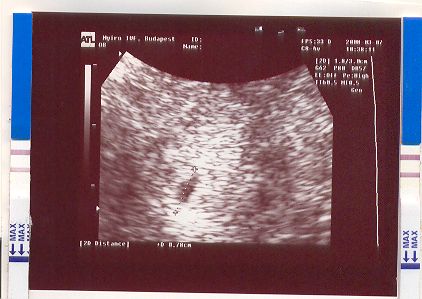

Olyan messze van még a 17-e, amikor ismét láthatom saját szememmel, hogy minden rendben van.